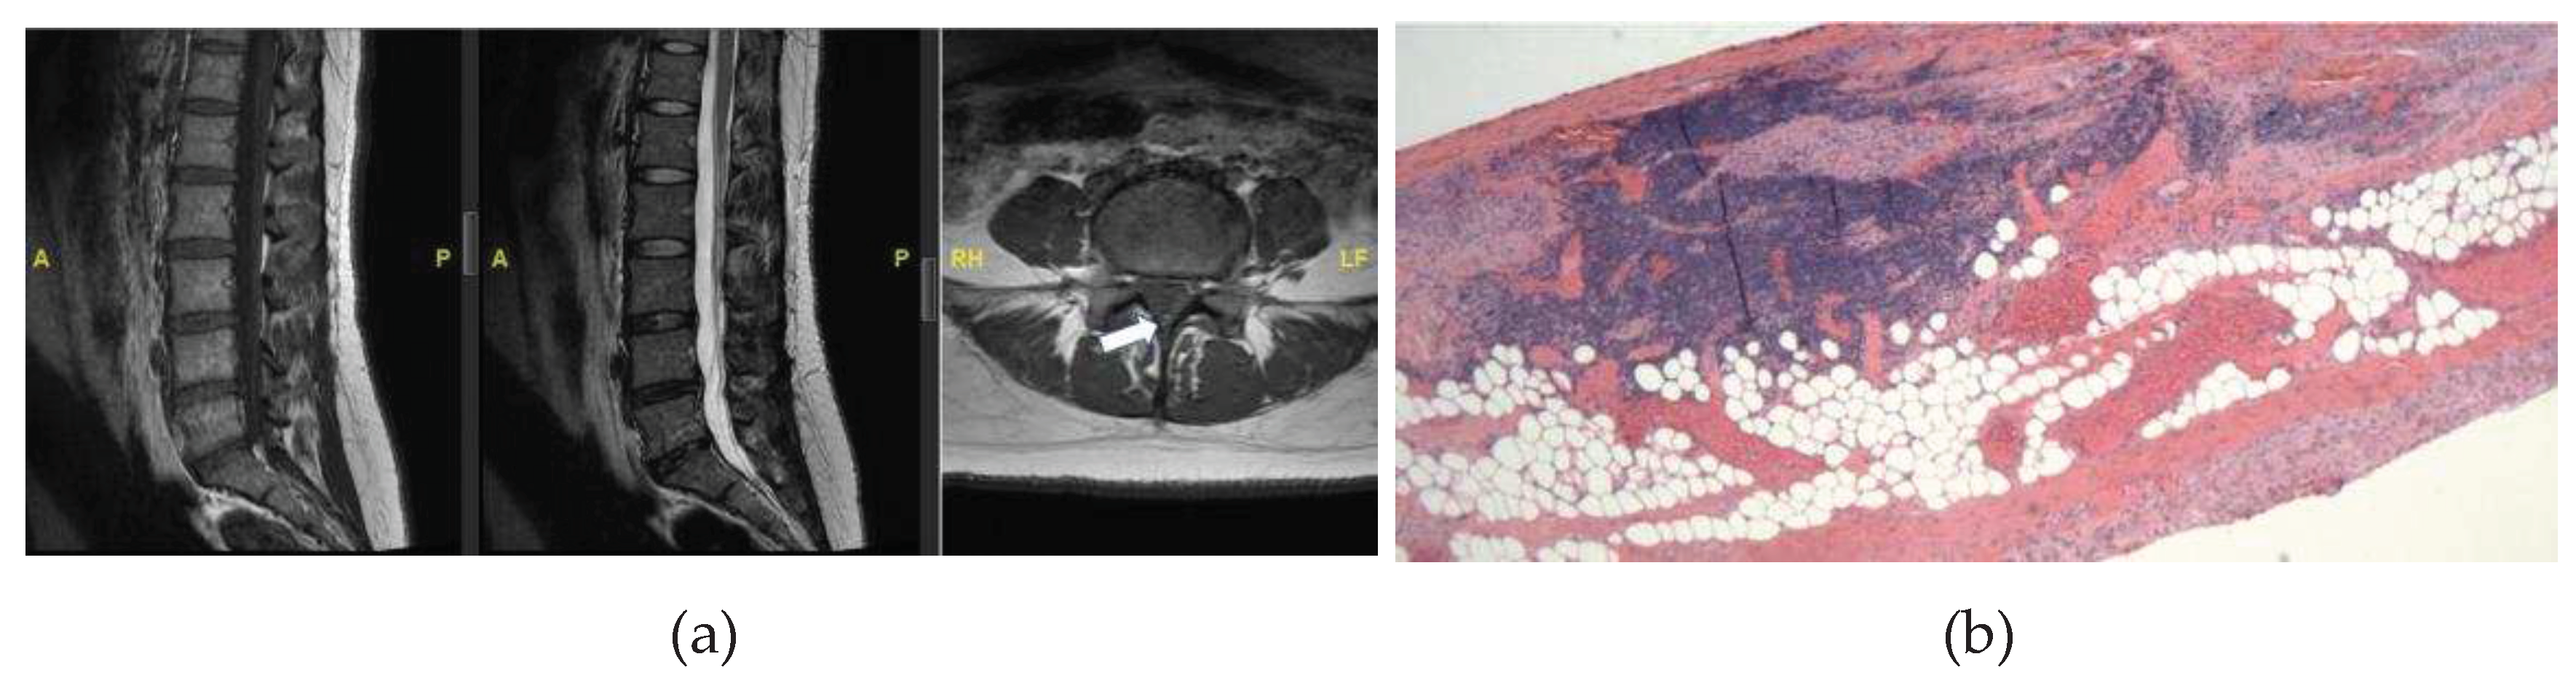

This is a case of a 53-year-old male with prior lumbar 4-5 transforaminal lumbar interbody fusion who presented with new onset of lower lumbosacral back pain, bilateral leg pain and numbness, and urinary incontinence and urgency. On physical exam, his right leg strength is 4 out of 5 in the hip flexion and knee extension. He is numb to touch and has increased tone bilaterally. His reflexes are 1+ bilaterally, with no foot clonus. He had an MRI of the lumbar spine which revealed a thickened filum terminale and conus terminating at the L2/L3 disc space (Figure 3A). The patient then underwent a lumbar 2-4 laminectomy for resection of filum terminale with no complications.

Histopathological analysis revealed fragments of fibrovascular and adipose tissue with embedded and adjacent ependymal cells and peripheral nerve twigs, and notably large, thick-walled, congested blood vessels (Figure 3B). Elastin stain showed a blood vessel with an internal elastic lamina, confirming its arterial origin (Figure 3C,D). This was interpreted as an arteriovenous malformation.

Figure 3. MRI (a) and histopathological examination of the FT (b-c). (A) Sagittal T1 (left), T2 (middle), and axial T1 sequence (right) reveals hyperintense signal of the filum (arrow), suggestive of thickened FT. (B) Fatty FT with several large, thick-walled, congested blood vessels, suggestive of a venous congestion. H&E stain, x40 (C) Low power of an elastic stain demonstrating a blood vessel with an internal elastic lamina, confirming its arterial origin. This suggests signs of venous congestion. x40.